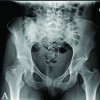

A 16-year-old male presented with complaints of deformity over his right knee for the past 2 years, associated with altered gait for the same period. He gives a history of a road traffic accident 2 years back, when he sustained a closed injury to his right knee. He was treated with indigenous splinting for 45 days, after which he was allowed to weight-bear and walk. On starting to weight bear, he noticed the deformity over his right knee. He was unable to extend his right knee fully, and his gait had changed following the injury. He was initially treated elsewhere with physiotherapy, but had no improvement in deformity, even though pain subsided. Even though he was managing functionally well with the deformity, he found it cosmetically displeasing to walk with the deformity. On examination, he had a short limb gait, a FFD of his right knee of around 30°, and multiple healed scars over his right knee were present. Bony thickening and broadening were felt over the distal femur. The range of right knee flexion was from 30° to 120°. A 3 cm femoral segment shortening was present on the right side. Distal neurovascular status was intact. Radiograph of right knee anteroposterior (AP) and lateral views (Fig. 1) were taken and showed a malunited fracture of the distal femur with open physis of the proximal tibia and fibula.

Figure 1 Presenting right knee radiograph

The distal femur physis was not clearly visible, suggesting that the injury was a distal femur physeal injury. Full-length radiographs of both lower limbs (Figs. 2) spanning from the hips to the ankles were taken to assess the mechanical axis of both lower limbs and to identify the pathology.